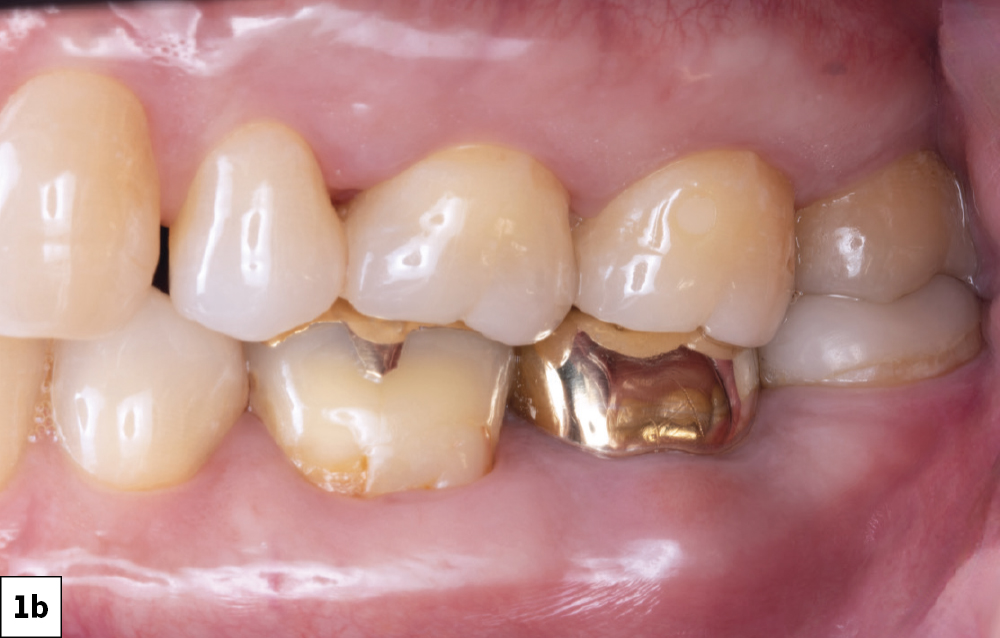

Pain in tooth #18 (Top View)

Pain in tooth #18 (Side View)

Figures 1a, 1b: The patient presented with complaints of pain in tooth #18. He previously had endodontic treatment done and presented with swelling of the facial gingiva, leading me to believe infection was present.